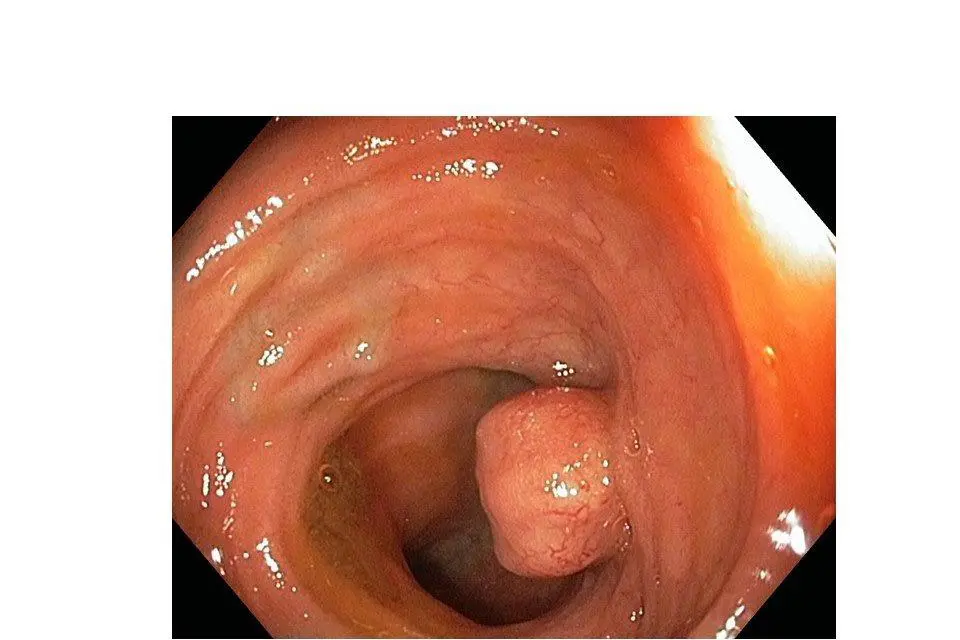

Koloskopi

Utføres ved at en slange med et videokamera i enden føres via endetarmsåpningen oppover i tykktarmen og inn i siste del av tynntarmen og gir god oversikt over disse områdene. Det er normalt ikke mulig å få oversikt over hele tynntarmen ved hjelp av denne undersøkelsen og gastroskopiundersøkelsen. Man kan ved denne prosedyren ta vevsprøver av sykelige tilstander som måtte påvises.

Foto: Oslo universitetssykehus

Bilde av en svulst i tynntarmen. Bildet er tatt under en kolonoskopi, og viser nevroendokrin svulst i siste del av tynntarmen. Svulsten måler 15 mm. Foto: Gasteroeneterlogisk undersøkelsesavdeling ved Oslo Universitetssykehus